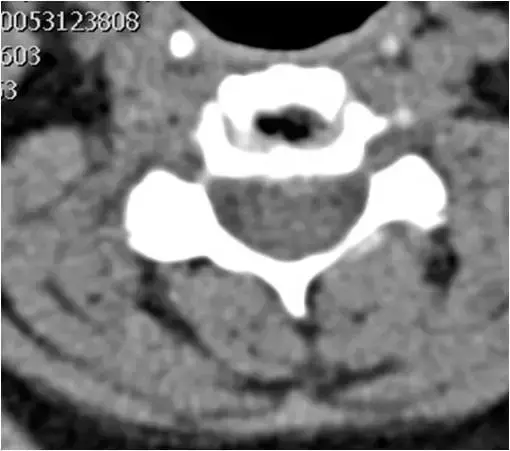

图23:下颈椎的轴向截面。广泛的骨赘形成和右钩椎关节肥大。硬膜囊颈髓的前部受压。确定脊柱狭窄。

图24:下颈椎的轴向截面。骨窗。与图像23相同的患者和相同水平。广泛的骨赘形成和右钩椎关节肥大。硬膜囊颈髓的前部受压。确定脊柱狭窄。